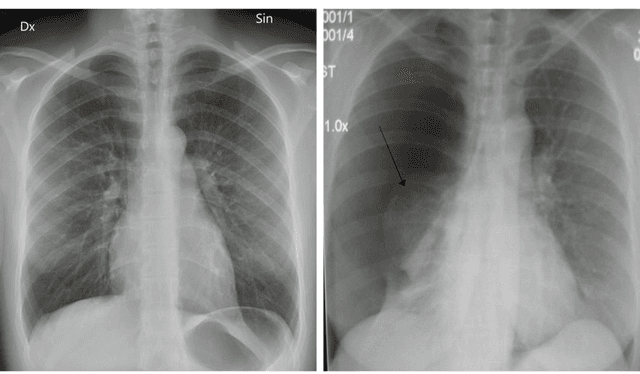

Pneumothorax is a relatively common disease, but in some cases, it may be difficult to find with chest radiography. In this paper, we propose a novel method of detecting pneumothorax in chest radiography. We propose an ensemble model of identical convolutional neural networks (CNN) with three different sizes of radiography images. Conventional methods may not properly characterize lost features while resizing large size images into 256 x 256 or 224 x 224 sizes. Our model is evaluated with ChestX-ray dataset which contains over 100,000 chest radiography images. As a result of the experiment, the proposed model showed AUC 0.911, which is the state of the art result in pneumothorax detection. Our method is expected to be effective when applying CNN to large size medical images.